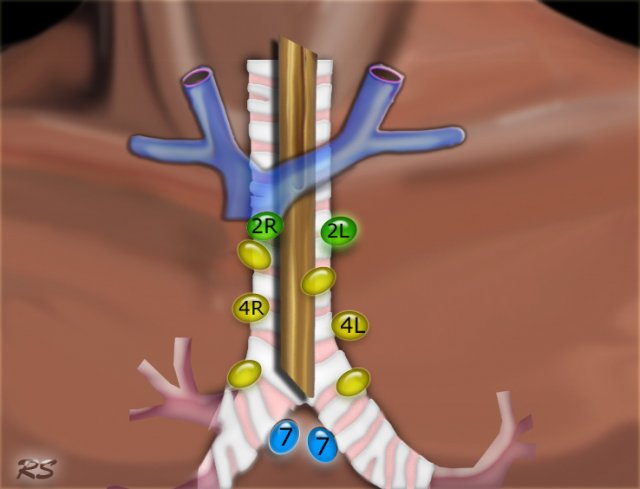

Superior Mediastinal Nodes 2-4

2R.Upper Paratracheal

2R nodes extend to the left lateral border of the trachea.

From upper border of manubrium to the intersection of caudal margin of innominate (left brachiocephalic) vein with the trachea.

2L.Upper Paratracheal

From the upper border of manubrium to the superior border of aortic arch.

2L nodes are located to the left of the left lateral border of the trachea.

4R.Lower Paratracheal

From the intersection of the caudal margin of innominate (left brachiocephalic) vein with the trachea to the lower border of the azygos vein.

4R nodes extend from the right to the left lateral border of the trachea.

4L.Lower Paratracheal

From the upper margin of the aortic arch to the upper rim of the left main pulmonary artery.

Inferior Mediastinal Nodes 7-9

7.Subcarinal

7. Subcarinal nodes

These nodes are located caudally to the carina of the trachea, but are not associated with the lower lobe bronchi or arteries within the lung.

Mediastinoscopy and EUS

Conventional mediastinoscopy

The following nodal stations can be biopsied by cervical mediastinoscopy:  the left and right upper paratracheal nodes (station 2L and 2R), left and right lower paratracheal nodes (station 4L and 4R) and the subcarinal nodes (station 7).